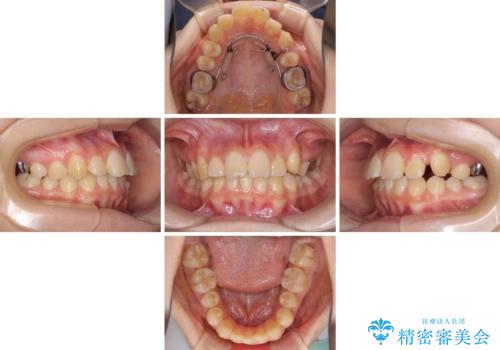

- 目立つ八重歯を改善したいとのことで来院された患者様です。

奥歯の咬み合わせは左右とも理想的なものでしたが、下顎前歯が1本欠損しているため、上下のバランスを保つことが難しい歯列でした。

唇を閉じたときに上顎前歯が下顎の唇に乗っかる印象があったため、八重歯の後方にある小臼歯を1本抜歯することとしました。

変則的な抜歯となるため、臼歯の咬合が理想的でなくなることが懸念されますが、インビザラインにて矯正治療を行うこととしました。